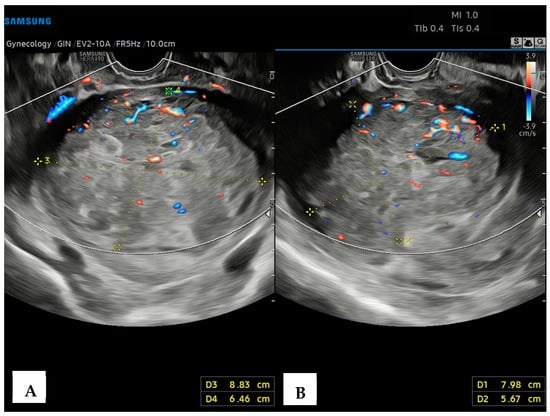

A 43-year-old healthy woman was referred to our Hospital in September 2022, following menometrorrhagia, pelvic pain and a recent diagnosis of uterine fibromatosis. Informed written consent for the publication of data was obtained. An expert transvaginal ultrasound with the Samsung HeraI10 was performed, revealing an enlarged, globose-shaped uterus, with a transmural (FIGO 3-5) uterine mass of the posterior body–fundus wall, which was hypoechoic, non-homogeneous, and without calcifications, cystic areas, or acoustic shadows, measuring 8.8 × 7.9 × 6.4 cm, and highly vascularized (Color Score 3-4, CS3-4), at the Color Doppler (CD) analysis (Figure 1).

Figure 1. Transvaginal ultrasound with Color Doppler analysis. (A) Longitudinal plane; (B) axial plane showing a hypoechoic, heterogeneous uterine mass, without calcifications or acoustic shadows, measuring (L × H × W) 8.8 × 7.9 × 6.4 cm. The Color Doppler analysis reveals an abundant perilesional and intralesional vascularization.